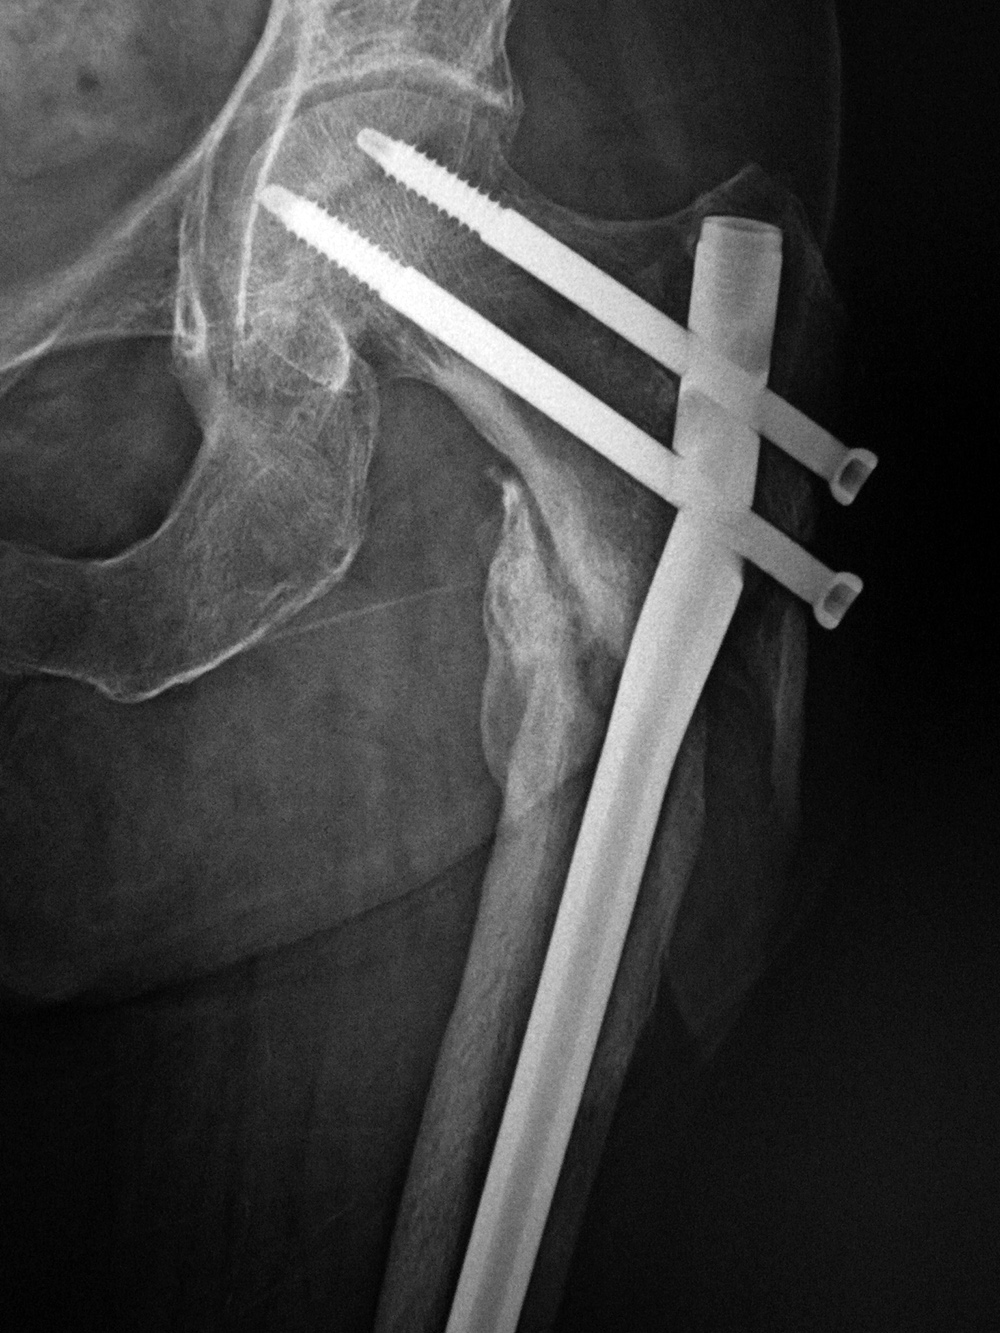

| Left hip cannulated screw fracture |

| 41 year-old man with chronic left femoral neck fracture and fracture of superior cannulated fixation screw. The partially visualized intramedullary nail is for an old femoral shaft fracture. |